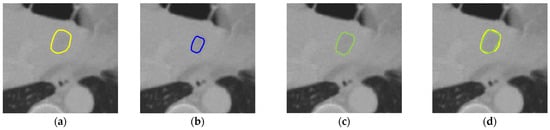

Background/Objectives: This study aimed to develop a fully automatic method for liver tumor segmentation based on our previously developed gradient-enhanced network G-UNETR++. Methods: The proposed method consists of segmentation of the full liver region from computed tomography (CT) images using G-UNETR++, [...] Read more.

Background/Objectives: This study aimed to develop a fully automatic method for liver tumor segmentation based on our previously developed gradient-enhanced network G-UNETR++. Methods: The proposed method consists of segmentation of the full liver region from computed tomography (CT) images using G-UNETR++, masking the CT images with the extracted liver region to exclude non-liver regions, and liver tumor segmentation from the masked CT images, also using G-UNETR++. To train and evaluate the model, a total of 131 CT scans (97 for training, 20 for validation, and 20 for testing) from the publicly available LiTS dataset were used. Furthermore, another public dataset, the 3DIRCADb dataset consisting of 20 CT scans was used for cross-validation of the effectiveness and generalizability of our method. Results: Experimental results showed that our method outperformed state-of-the-art models over both the LiTS dataset and the 3DIRCADb dataset, with an average dice score of 0.844 and 0.832 over the two datasets, respectively. Conclusions: The proposed method is effective in clinical application to help physicians with liver tumor diagnosis and treatment. Full article

Show Figures

Figure 1